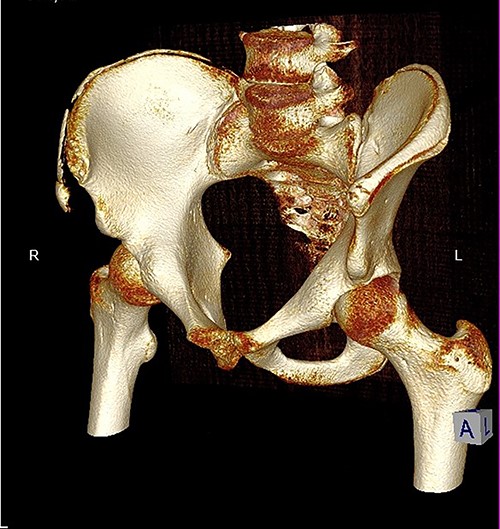

The anterior–posterior plain film X-Ray of pelvis demonstrated an avulsion fracture of the right ASIS and IC apophysis with 1.5 cm displacement (Fig. 1). Lateral view of the hip showed no extension into the joint. There was no radiological evidence of chronic overuse or previous injury. Computed tomography (CT) imaging was performed to better identify the injury; 3D volume reconstruction clearly demonstrated the unique fracture pattern of an ASIS avulsion in addition to an avulsion of the distal iliac apophysis extending ~5 cm with the described displacement (Figs 2–4).

3D reconstruction of tomographic CT scan illustrating avulsion fracture of ASIS and IC apophysis with its latero-inferior displacement (R - Right, L - Left, A - Anterior).